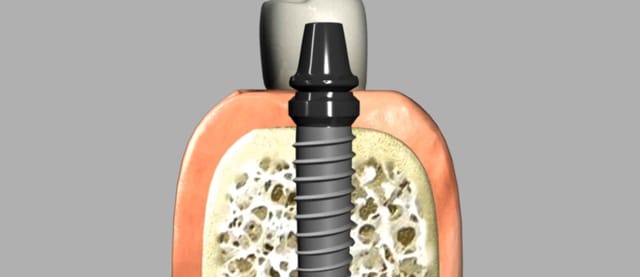

An implant is a titanium "root" which can be placed into the jawbone. A single tooth implant can be used to support a crown in cases where one missing or damaged tooth needs to be replaced.